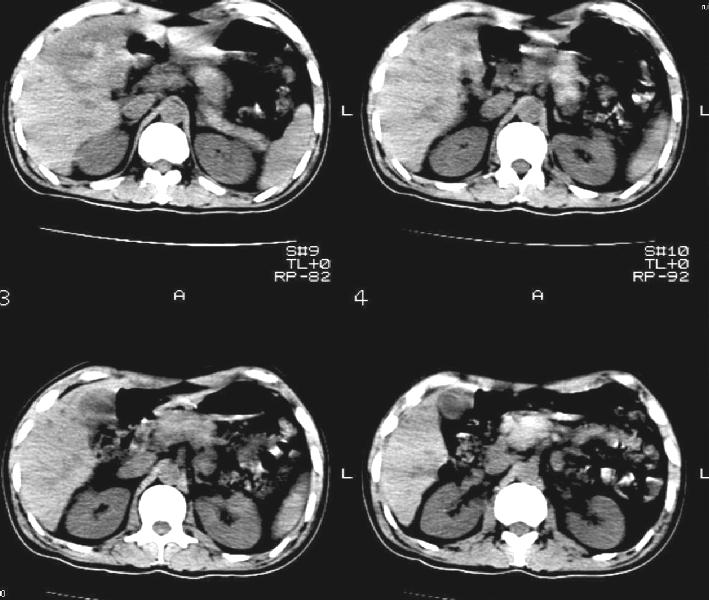

标题: CT11005:男,40岁,左股骨骨折术后10余天,现在感右上腹痛。

b超:右前叶不均质占位。是肿瘤出血还是肝挫伤?以前没有症状啊,10多天后腹部才疼痛。

肝挫裂伤伴血肿形成.

右侧胸腔积液,又有外伤史,肝脏混杂密谋影,考虑肝挫伤可能性大.

肝右叶脓肿可能,请结合临床或增强检查

右侧胸腔积液,又有外伤史,肝脏混杂密度影,考虑肝钝性挫伤可能性大。

建议增强扫描